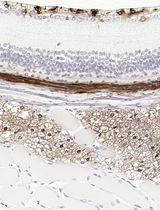

采用 Davidson 固定液和黑色素漂白法优化小鼠眼组织切片的免疫组化染色

Anne Nathalie Longakit [...] Catherine D. Van Raamsdonk

2025年11月20日 812 阅读